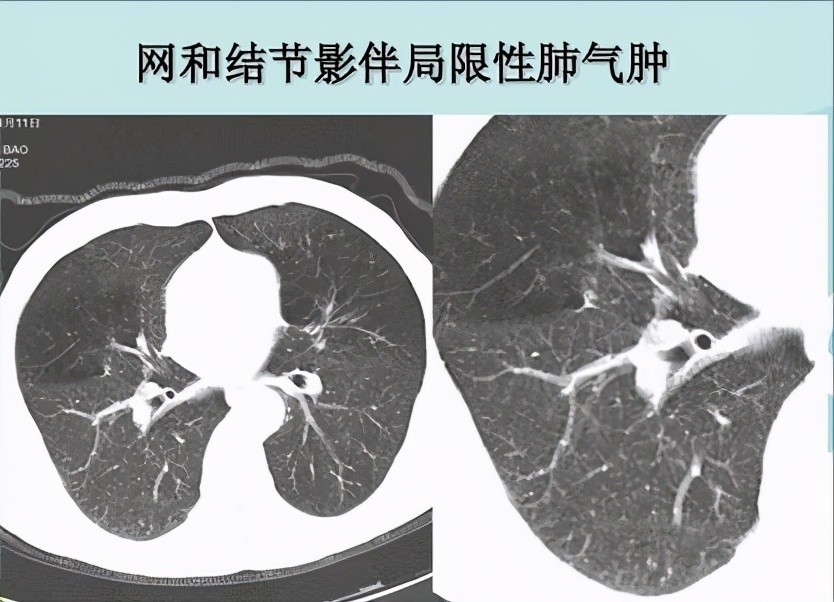

4.局限性肺气肿

局限性肺气肿是指CT所发现的局灶性肺气肿改变 , 面积不大 , 可伴有局部的肺大泡 。 当局部的某些气管狭窄 , 就只会引起局限性肺气肿 。 多见于长期吸烟者 , 另外支气管哮喘 , 慢性阻塞性肺病也有可能导致局限性肺气肿 。 大部分情况下 , 局限性肺气肿没有明显临床症状 , 也不需要特殊治疗 , 对肺功能影响较小 。 只需要注意平时肺部保养 , 减少有毒有害气体对肺部的损害 , 避免受凉、感冒并戒烟 。